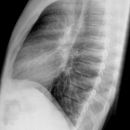

Thorax p.-a.

Streng symmetrisch, Schulterblätter außerhalb der Lunge. Atemphase: maximale Inspiration. Bei Verdacht auf Pneumothorax in maximaler Expiration die Aufnahme durchführen.

Abgebildet müssen sein: beide Lungenflügel, PC-Winkel und Lungenspitzen. Die ersten 3-5 Rippen sollten schwach erkennbar sein, die inneren Scapularänder sollten außerhalb des Thorax liegen.